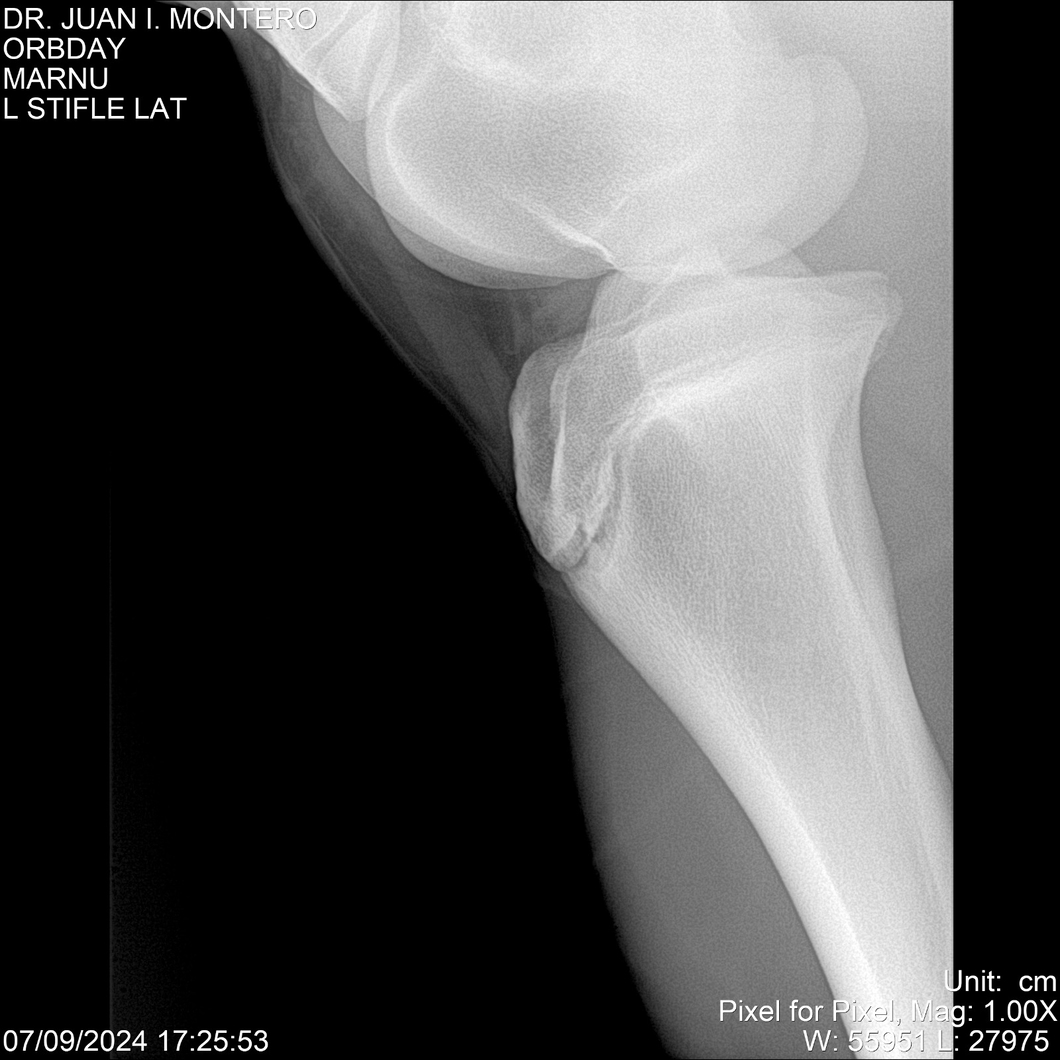

• Empresa: Abelenda N. R., Walter Hugo